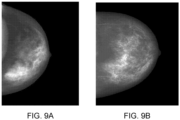

• Figure 10 shows an example of two breasts: one shown in an image on the left is dense with low a BPE reading and the other shown in an image shown on the right is fatty with high BPE reading.

• the tissue structure of the right breast is more complicated than the tissue structure of the left breast, which further supports our understanding of a possible positive correlation between tissue pattern complexity and BPE category.